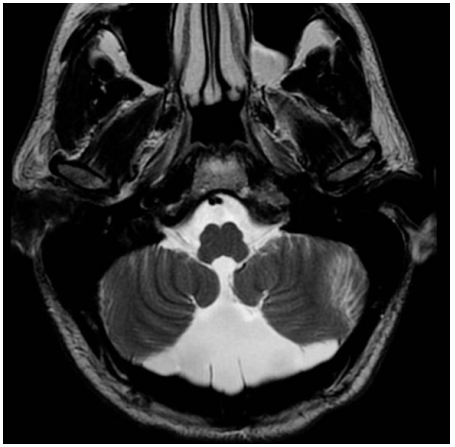

Paciente masculino, de 14 anos, vem realizar ressonância magnética do encéfalo, que apresentou imagem típica de Megacisterna magna. Sobre esse diagnóstico, assinale a alternativa correta.

Axial T2